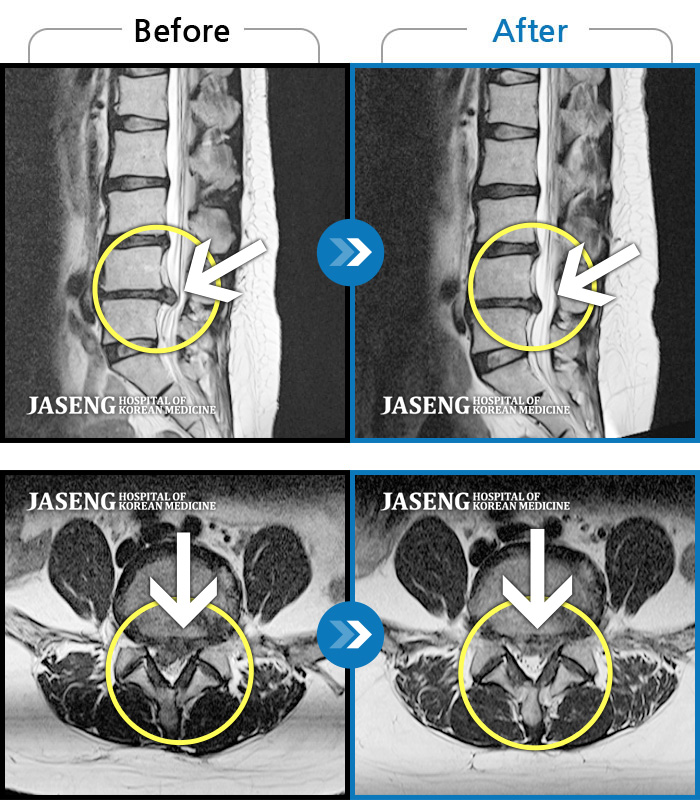

MRI 치료사례

기침하면 허리 통증 발생, 몸을 비틀면 우측 허벅지에서 종아리까지 통증